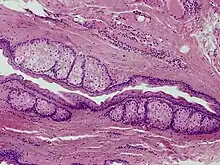

Steatocystoma multiplex is a benign, autosomal dominant congenital condition resulting in multiple cysts on a person's body. Steatocystoma simplex is the solitary counterpart to steatocystoma multiplex.[2]

The cysts are mostly small (2–20 mm) but they may be several centimetres in diameter. They tend to be soft to firm semi-translucent bumps, and contain an oily, yellow liquid. Sometimes a small central punctum can be identified and they may contain one or more hairs (eruptive vellus hair cysts). They may become inflamed and heal with scarring, like acne nodules (see nodulocystic acne and hidradenitis suppurativa).

Steatocystomas are thought to come from an abnormal lining of the passageway to the oil glands (sebaceous duct).